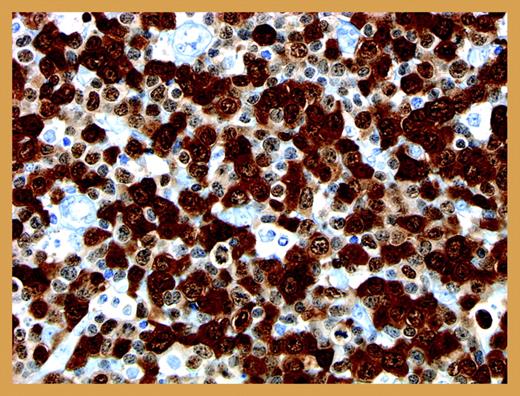

Anti-ALK immunostain of a typical NPM-ALK-positive anaplastic large-cell lymphoma. Illustration by Dr Mihaela Onciu, St Jude Children's Research Hospital.